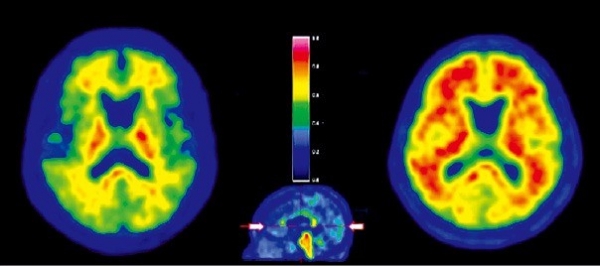

아밀로이드 PET검사는 알츠하이머병 또는 인지장애 의심 환자를 대상으로 뇌 부위를 촬영하는 양전자 방출 단층촬영 검사다.

독성단백질은 알츠하이머 치매의 특징으로 증상이 없는 초기부터 나타난다. 이 독성단백질의 쌓이는 정도를 영상으로 보면 알츠하이머 치매여부와 인지기능 감퇴 여부를 알 수 있다.

치매를 진단하는 방식으로는 혈액검사나 MRI 등이 있지만, 아밀로이드 PET검사는 기존 검사보다 진단 정확도가 높다는 것이 최대 장점이다.